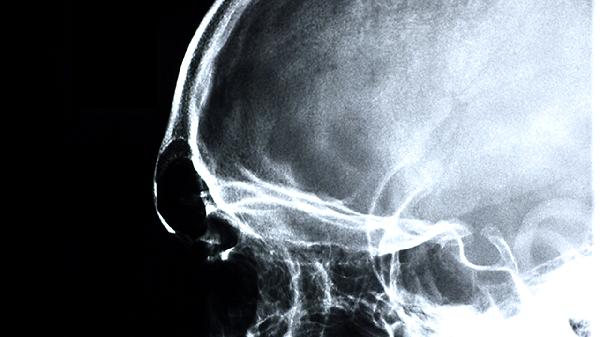

脑外伤后遗症是因为错过了治疗的最佳时期,而引起的脑组织功能异常,常见的后遗症有很多,比如偏瘫、说话不利索,行动不利索等等。那么脑外伤后遗症吃什么药?一起通过下文来好好了解吧。